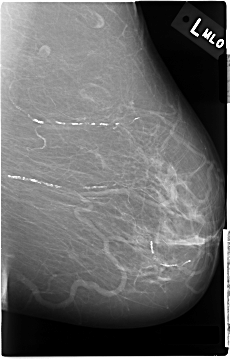

C_0031_1.LEFT_MLO

LEFT_MLO LINES 4656 PIXELS_PER_LINE 2984 BITS_PER_PIXEL 12 RESOLUTION 50 NON_OVERLAY